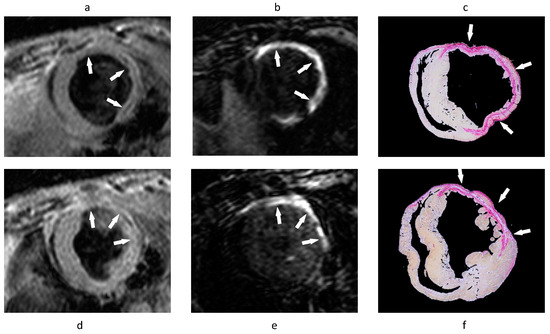

- Phinikaridou, A.; Andia, M.E.; Indermuehle, A.; Onthank, D.C.; Cesati, R.R.; Smith, A.; Robinson, S.P.; Saha, P.; Botnar, R.M. Vascular remodeling and plaque vulnerability in a rabbit model of atherosclerosis: Comparison of delayed-enhancement MR imaging with an elastin-specific contrast agent and unenhanced black-blood MR imaging. Radiology 2014, 271, 390–399. [Google Scholar] [CrossRef]

- Phinikaridou, A.; Lacerda, S.; Lavin, B.; Andia, M.E.; Smith, A.; Saha, P.; Botnar, R.M. Tropoelastin: A novel marker for plaque progression and instability. Circ. Cardiovasc. Imaging 2018, 11, e007303. [Google Scholar] [CrossRef]